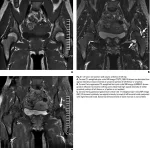

痛みと外観, MRI所見からは, グロームス腫瘍という血管性の良性腫瘍が疑われました.